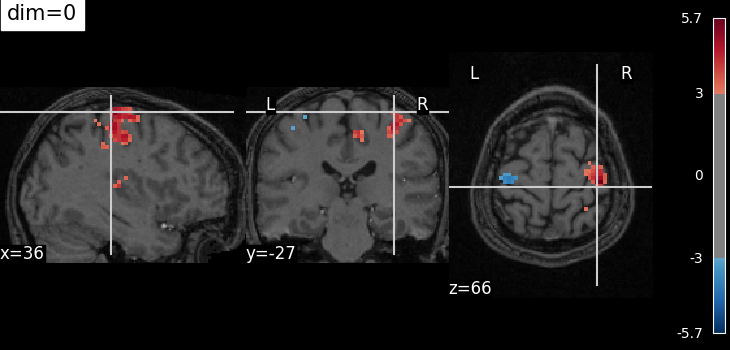

The dim argument controls the contrast of the background.

dim modifies the contrast of this image: dim=0 leaves the image unchanged, negative values of dim enhance it, and positive values decrease it (dim the background).

Plotting with no change of contrast in background image with dim=0¶

plot_stat_map(

localizer_tmap_filename,

bg_img=localizer_anat_filename,

cut_coords=cut_coords,

threshold=3,

title="dim=0",

dim=0,

)

<nilearn.plotting.displays._slicers.OrthoSlicer object at 0x7f1f0cd53370>